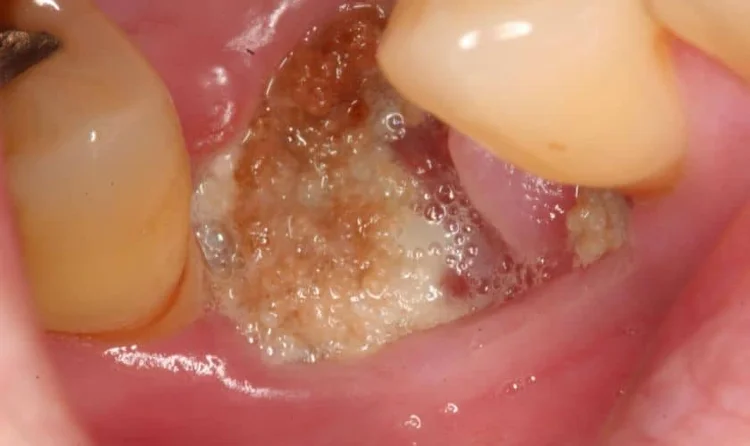

After procedures like tooth extraction or surgical treatment, a blood clot forms to protect the underlying bone and tissue. If this clot dislodges or if oral hygiene is compromised, bacteria can colonize the site and trigger infection.

- Pus discharge or foul taste

- Drainage of infection – If pus is present, relieving pressure is often the first step.